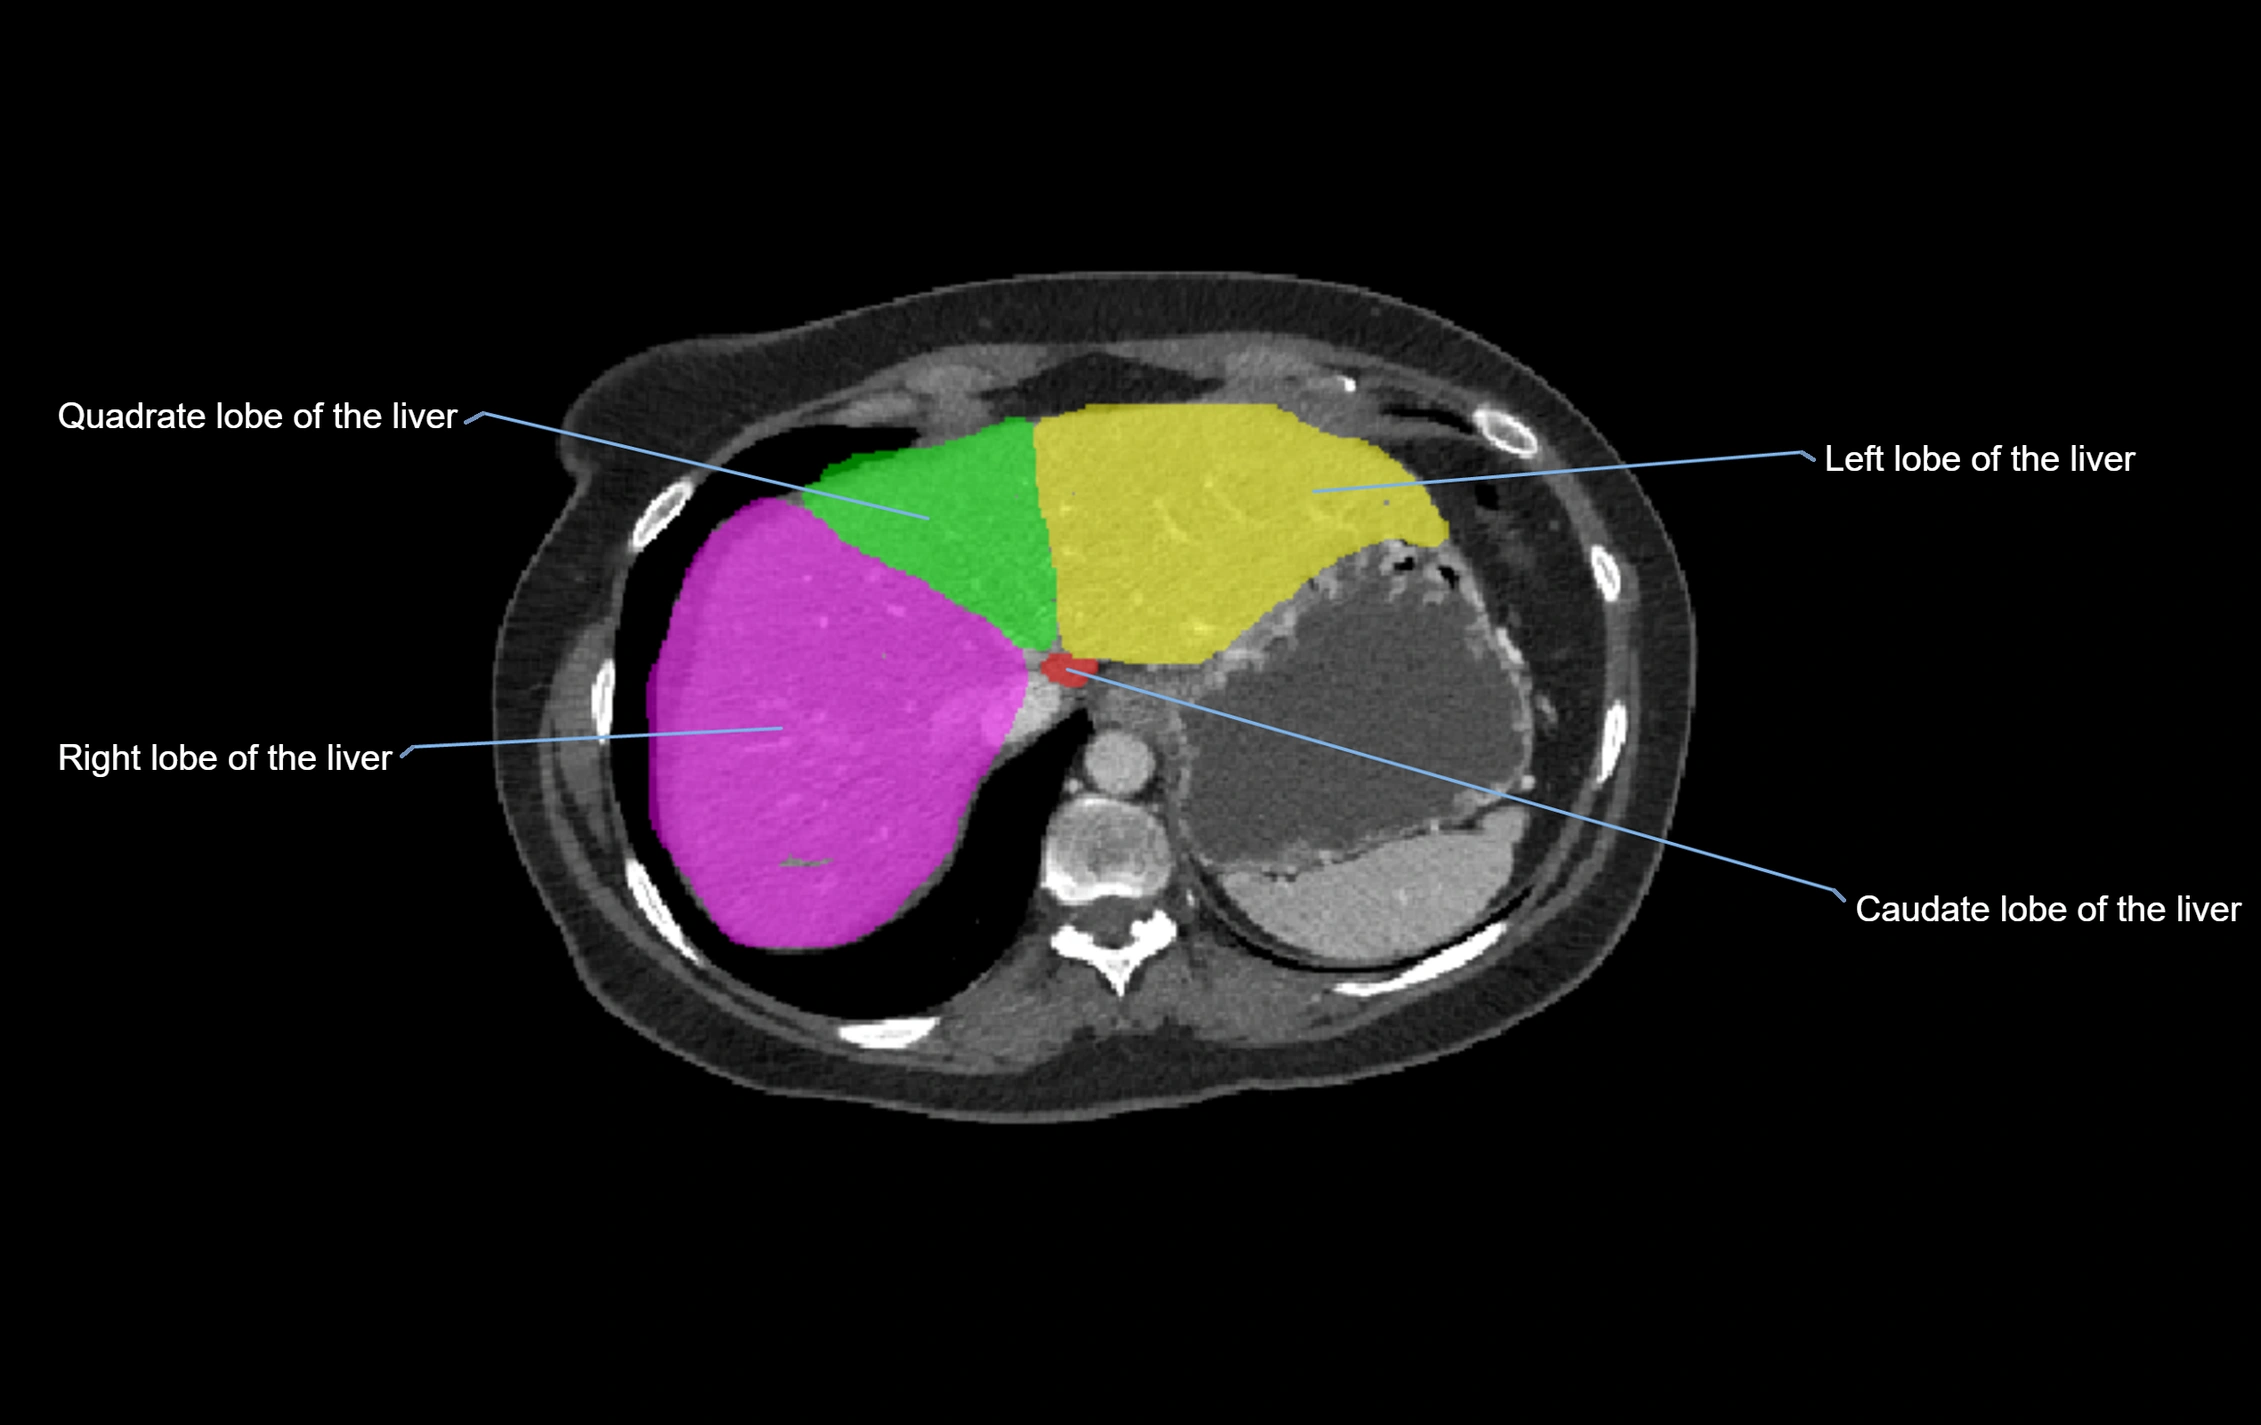

The caudate lobe of the liver is a distinct anatomical subdivision of the liver, designated as segment I in Couinaud’s classification. It lies on the posterior surface of the liver, between the fissure for the ligamentum venosum (left boundary) and the groove for the inferior vena cava (IVC) (right boundary). Superiorly, it is related to the posterior liver surface, and inferiorly it is separated from the left lobe by the porta hepatis.

The caudate lobe is unique because it receives dual portal venous and arterial inflow from both the right and left portal veins and hepatic arteries. It also has independent venous drainage directly into the IVC via multiple small hepatic veins, unlike other lobes that drain through the three main hepatic veins.

This anatomical autonomy makes the caudate lobe especially significant in liver surgery, transplantation, and hepatic venous outflow obstruction syndromes (e.g., Budd–Chiari syndrome). Enlargement of the caudate lobe is a characteristic imaging feature in chronic liver disease and cirrhosis.

CT Appearance

CT Pre-Contrast:

• Caudate lobe appears as a soft-tissue density, isodense to the rest of the liver

• Enlargement may be appreciated in cirrhosis or Budd–Chiari syndrome

CT Post-Contrast:

• Homogeneous enhancement in the portal venous phase, similar to rest of liver

• Independent venous drainage into the IVC may be visualized

• Lesions follow characteristic CT enhancement patterns (HCC: arterial hyperenhancement with washout; hemangiomas: peripheral nodular enhancement with centripetal fill-in)

CT Venous Phase (functional significance):

• Caudate lobe often enhances relatively more than other lobes in Budd–Chiari syndrome, due to preserved venous outflow